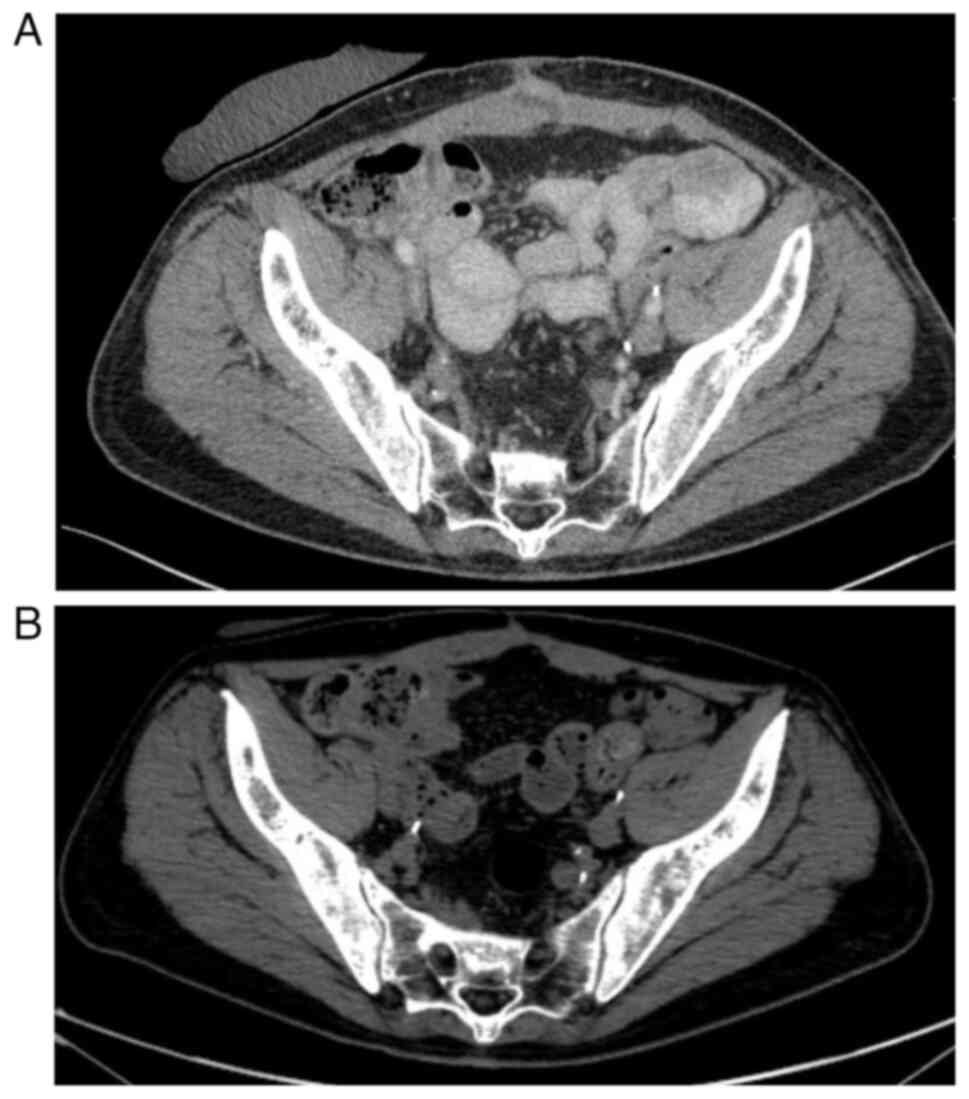

The first follow-up CT scan performed in April 2023 showed progression of the disease: Foci of sclerotic remodeling were found in the vertebrae, ribs and pelvis (suggestive of metastasis; Fig. 10A), though no local recurrence, lymphadenopathy or hydronephrosis were observed. The metabolically active nature of the changes observed on the CT scan was confirmed by a bone scintigram (data not shown), which diagnosed multifocal active metastasis to the skeletal system. For this reason, the patient qualified for four cycles of chemotherapy (consisting of gemcitabine and carboplatin) and received bisphosphonates as prophylaxis to prevent bone loss and reduce the risk of skeletal-related events. After four cycles of chemotherapy, the patient underwent four cycles of maintenance treatment with avelumab immunotherapy. Follow-up computed tomography examinations performed in December 2023 revealed further progression of the disease (Fig. 10B). The patient's general health gradually deteriorated and the patient did not return for further therapy.

Figure 10.

(A) First follow-up CT scan. Progression of the disease: Foci of sclerotic remodeling found in the pelvis. (B) Follow-up computed tomography performed in December 2023-further progression of the disease.